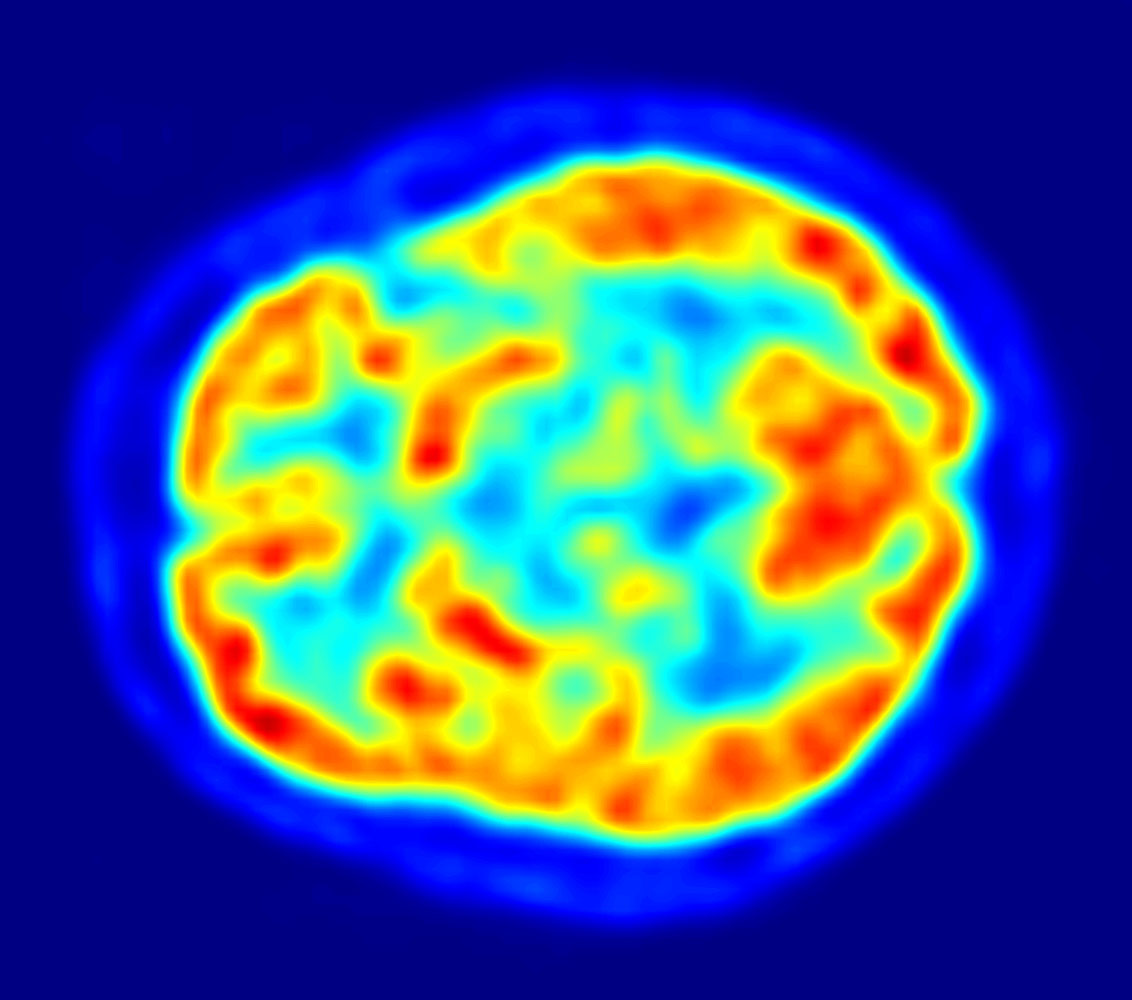

[18F]플루오로데옥시글루코스 (FDG)를 이용한 PET 영상은 뇌가 정상적으로 포도당을 빠르게 사용한다는 점을 이용한다. 뇌의 표준 FDG PET는 지역 포도당 사용량을 측정하며 신경병리학적 진단에 사용될 수 있다.[17]

알츠하이머병과 같은 뇌 병변은 포도당과 산소의 뇌 대사를 모두 크게 감소시킨다. 따라서 뇌의 FDG PET는 알츠하이머병을 다른 치매 과정과 구별하고 조기에 진단하는 데 사용될 수 있다. 알츠하이머병 진단을 위해 아밀로이드-베타 플라크를 영상화하는 방사성 추적자에는 플로르베타피르, 플루테메타몰, 피츠버그 화합물 B(PiB) 및 플로르베타벤이 있으며, 이들은 모두 뇌에서 아밀로이드-베타 플라크를 감지하는 데 사용된다.[18]

뇌 내 신경 활동이 높아지면 해당 부위의 대사량이나 혈류량이 증가하므로, 파악하고자 하는 지표에 맞춰 위에 언급한 추적자를 선택함으로써 간접적으로 뇌 내에서 활동이 활발한 부위를 특정할 수 있다.

- 포도당 대사량을 측정하고자 할 때에는 추적자로 18F-플루오로데옥시글루코스영어 (FDG)를 주로 사용한다. 18F-FDG영어는 포도당과 유사한 물질에 방사성 불소(18F)를 붙인 것으로, 체내에서는 포도당과 마찬가지로 흡수되지만, 포도당과 달리 18F-FDG영어는 소변과 함께 신장, 요관, 방광을 통해 체외로 배설된다.[96][97]